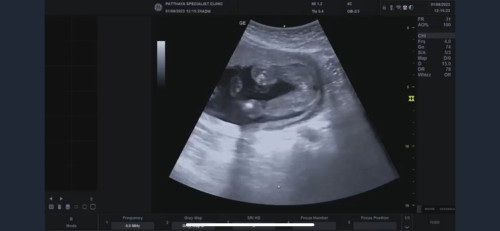

16วีค ลุ้นว่าเป็นผู้ชายตอนนั้นหนีบขาอยู่ หมอบอกไม่แน่ใจ วันนี้20วีคไปซาวด์มาอีกครั้งหมอบอกว่าเรียบมากครับคุณแม่ ยินดีด้วยได้ลูกสาว ใจนี่ก็อยากได้ผู้ชายแต่เห็นลูกสาวบ้านอื่นแต่งตัวคาซาอี้มากก เลยอยากได้ลูกสาวด้วยแหละคะ ส่วนอิพ่อจะร้องเลย เพราะทั้งบ้านมีพ่อเป็นผช.คนเดียว พี่ก็เป็นผญ หมด หลานก็เป็นผญ แล้วก็แม่ มีโอกาสจะจู๋โผล่มาไหม เพราะเพื่อนเราเขาก็บอกว่าหมอซาวด์บอกเป็นหญิง พอ หลายวีคผ่านไปซาวด์อีกเป็นชายเฉย